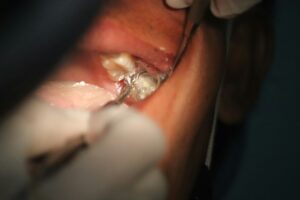

How Dental Crowns Help When a Tooth Is Too Damaged to Fill

When a tooth gets too worn down or broken to hold a filling, it becomes more than just a small dental issue. Fillings are useful for cavities and minor repairs, but there comes a point when a tooth needs something stronger. That’s when we may look to a dental crowns service to fully restore it.…